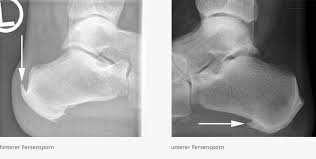

Den gesamten Komplex bilden außerdem Gelenke Fußwurzelgelenke Gelenke der Mittelfußknochen und Zehengelenke viele für die. Eine weitere Ursache für Schmerzen an der Fußaußenseite ist die Fraktur des fünften Mittelfußknochens. Der menschliche Fuß besteht aus 26 Knochen.

Den gesamten Komplex bilden außerdem Gelenke Fußwurzelgelenke Gelenke der Mittelfußknochen und Zehengelenke viele für die. Die Basen der Mittelfußknochen werden darauf mit der Fußwurzelknochenreihe mit Schrauben versorgt. Hühneraugen und Schwielen sind dicke harte Hautpartien die sich häufig an der Seite deiner Füße und Zehen entwickeln. Andere Erkrankungen der Füße entstehen durch Krankheiten die viele Bereiche des Körpers betreffen wie Diabetes mellitus Gicht oder andere Arthritisformen. Den gesamten Komplex bilden außerdem Gelenke Fußwurzelgelenke Gelenke der Mittelfußknochen und Zehengelenke viele für die. Das untere Sprunggelenk verbindet das Sprungbein mit den Knochen der Fußwurzel und dem Fersenbein. Sie unterstützen uns bei der Beantwortung der Fragen welche Seiten am beliebtesten sind welche am wenigsten genutzt werden und wie sich Besucher auf der Website bewegen. Trochanter grch der Rollhügel sd am Oberschenkelknochen. Fuß- und Knöchelbrüche sind recht häufig.

Trochanter Trochanter der Rollhügel su. Jeder Teil des Fußes ob Knochen Muskel Gelenk Sehne oder Band kann betroffen sein. Verschiedene Gelenke Muskeln Sehnen Bänder Nerven und Blutgefäße sorgen dafür dass die Füße zugleich stabil und beweglich sind. Klicken und ziehen um das 3D-Modell auf der Seite. Länger bestehende Schmerzen an der Fußaußenkante sind nicht physiologisch und müssen aufgrund möglicher behandlungsbedürftiger Ursachen ärztlich abgeklärt werden. Die Bruchstelle liegt hier meist an der Basis des zweiten Mittelfußknochens. Trochanter lat Rollhügel s.